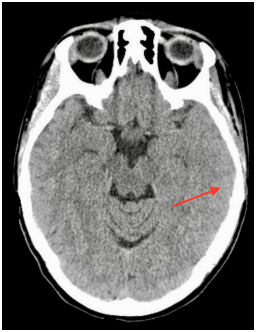

A 40-year-old woman suffered a left parieto-temporal TBI after a fall. The event was preceded by a transient loss of consciousness followed by spontaneous recovery. She complained of nausea and a light tension-type holocranial headache. The pain was relieved with analgesic and antiemetic drugs. She had a Glasgow Coma Scale (GCS) of 15 and an unremarkable remaining physical and neurological examination. The electrocardiogram and echocardiogram were both unremarkable. The cranial CT scan showed a left linear fracture of the petrous temporal bone (Figure1A), a 3-millimetre left subdural hematoma (SDH) and pneumocephaly (Figure 1B). Her past medical history was relevant: she had taken the same brand of oral contraceptives for the previous 20 years.

Figure 1A CT scan showing left linear fracture of the petrous temporal bone.

Figure 1B CT scan showing left temporal pneumocephaly and milimetric SDH.